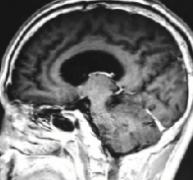

听神经瘤5厘米能手术吗?四种常用的肿瘤分级是Sterkers分类,House分类,Koos分类和Samii分类(见图1),5厘米的听神经瘤属于巨瘤范畴。由听神经瘤引起的症状取决于肿瘤的大小和生长。...

另一方面,到达三叉神经的神经鞘瘤的特征是疼痛和面部麻木。同样,Samii和Matthies报道,大约1%-3%的前庭神经鞘瘤患者出现三叉神经痛症状。目前,医学影像学,特别是核磁共振成像,...